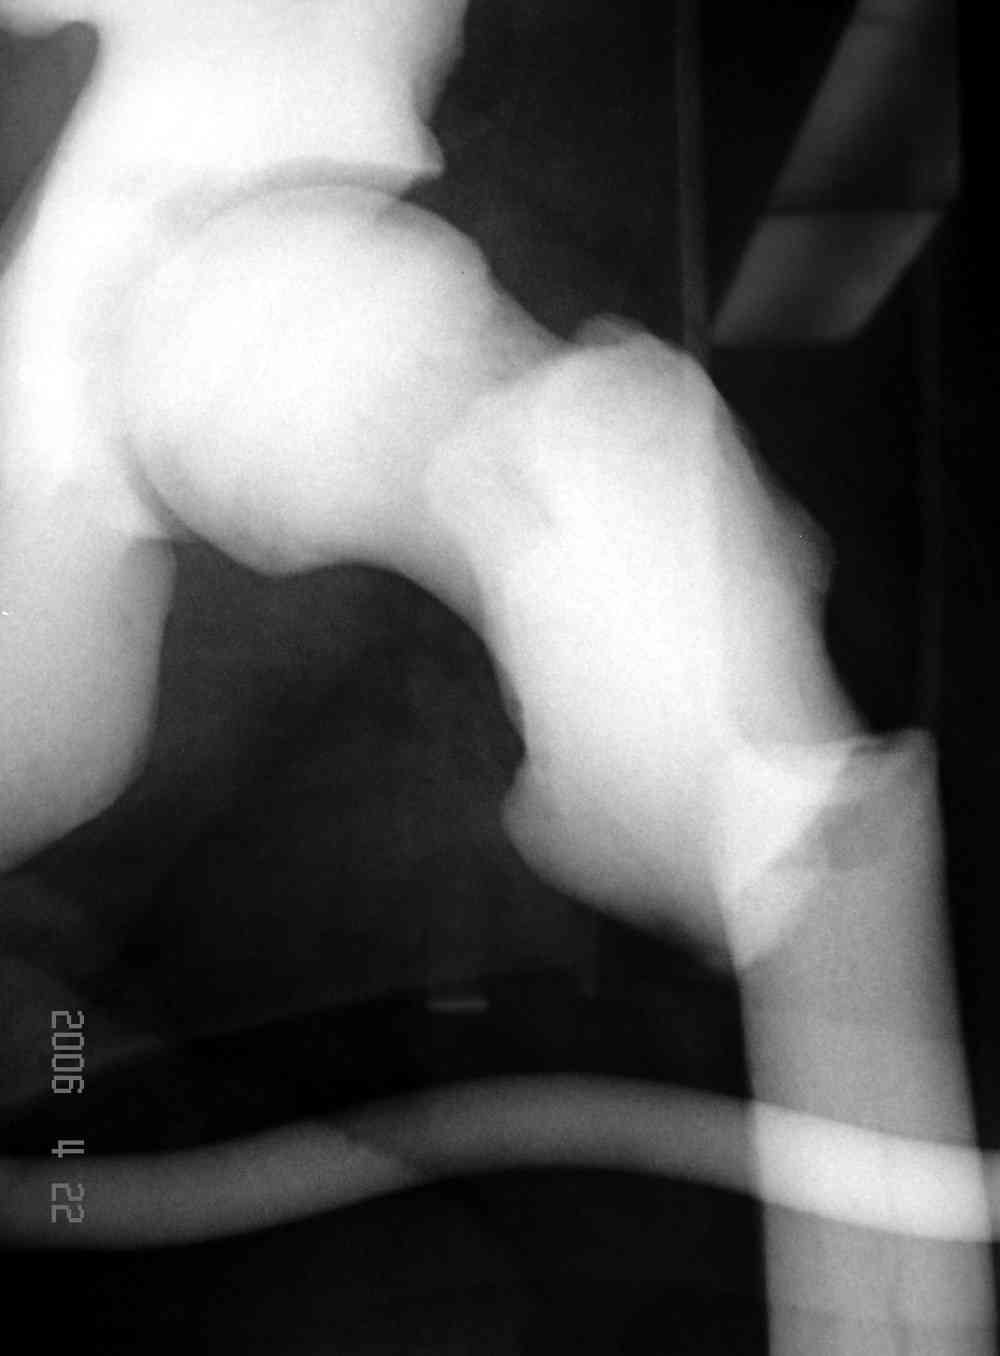

Здесь у меня дополнительные снимки с большим разрешением и в разных режимах, а то те дигитал снимки совсем очень блеклые, может, эти изображени изменят выбор тактики

После неудачной попытки скелетного вытяжения в первом мед.учреждении, после осмотра снимков и изучения истории, поставили диагноз “Остеопетроз” или мраморная болезнь, редкая наследственная костная паталогия, где имеется нарушение формации остеокластов.

Конечно, было бы идеальным применение интрамедуллярного остеосинтеза, но учитывая прежний собственный опыт (лечил перелом бедра) и

публикации, предупреждающие о трудностях при обработке кости (иногда из-за неподготовленности инструментария результатом была неадекватная фиксация перелома, или перенос операции из-за фактора усталости оперирующего персонала), решили применить пластину (и в этом же случае был выбран Synthes plate, так что представитель за два дня

зароботал... на десерт тоже).

Заказаны были дополнительные различные дрели, и на следующий день, усиленной бригадой, больного прооперировали, потратив на каждое отверстие около 25-35 минут, хотя сверлили с охлаждением по нарастающей по диаметру сверл и с их заменой каждые 2 мм сверления.

Теперь стоит задача со сращением перелома, из-за отсутствия литературных данных по применению костных стимуляторов при остеопетрозе, и не зная как поведет в этой среде Grafton, все таки надеюсь, что даст толчок к стимуляцию, решил применить пастообразную деминерализованную костную матрицу, расположив спереди между отломками.